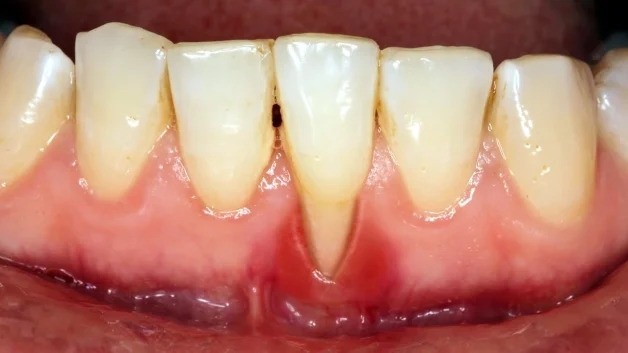

Cao răng để lâu có thể dẫn đến viêm lợi, viêm chân răng

– Viêm nướu: tình trạng nướu sưng, tấy đỏ, chảy máu… Thông thường ở những bệnh nhân viêm nướu do cao răng gây nên, nha sĩ sẽ thực hiện loại bỏ cao răng và sau đó có phương pháp chăm sóc đúng cách, nướu sẽ hồi phục lại rất nhanh. Ở những bệnh nhân đã chữa khỏi cần duy trì vệ sinh răng miệng đúng cách để làm chậm quá trình hình thành cao răng, tránh cao răng tích tụ quá dày khiến bệnh tái phát.

– Viêm nha chu: đây là tình trạng nặng nề hơn khi bệnh viêm nướu kéo dài mà không được chữa trị. Viêm nha chu sẽ khiến cho các mô nha chu (mô có tác dụng nâng đỡ và giữ chắc răng trên cung hàm) bị suy yếu, không thể giữ được răng ổn định, dẫn đến răng lung lay dẫn đến bị mất răng. Thậm chí ổ viêm nhiễm nặng còn có thể ảnh hưởng đến xương hàm, gây viêm xương hàm.